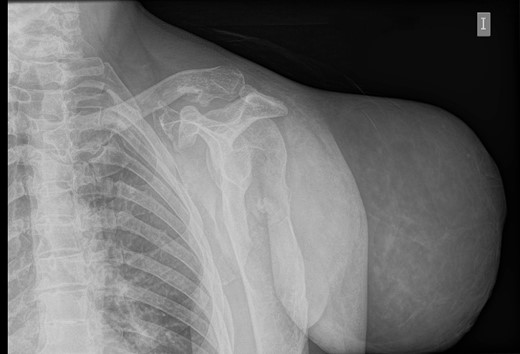

During the follow-up, a magnetic resonance (Figs 3 and 4) was performed describing a soft tissue lesion highly suggestive for liposarcoma as a first possibility diagnosis, with an addition image suggesting metastatic axillary lymph node. After the imaging results, biopsies were taken and analysed by the pathologist with a final diagnosis of PL.

Magnetic resonance imaging T2 with contrast: giant excrescent lesion of 19 × 18 × 14.4 cm of diameter located in the subcutaneous tissue of the posterior aspect of the scapula divided by multiple septums; axillary lymph node of ~0.9 cm; images compatible with liposarcoma with a metastatic axillary lymph node.